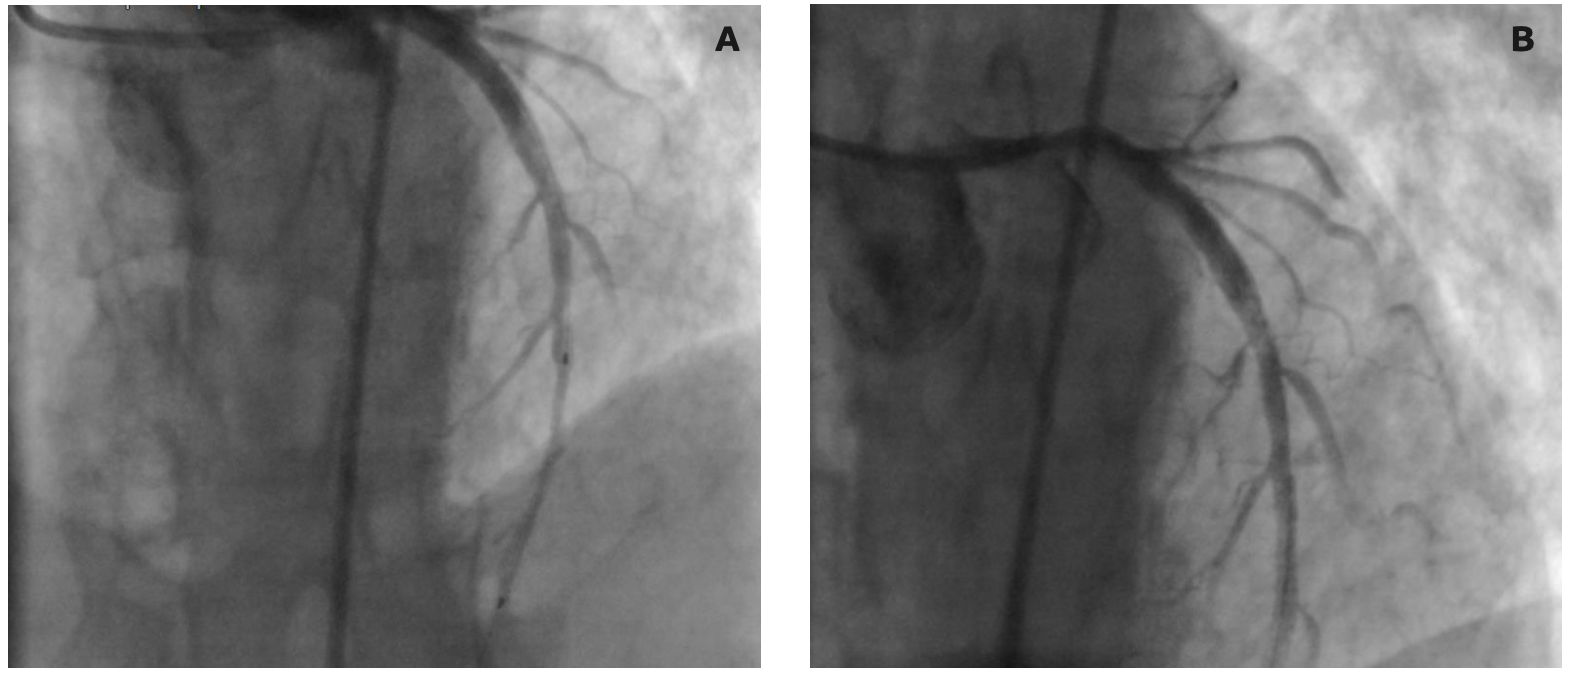

He was transferred to the cardiac catheterization lab with presumptive diagnosis of acute anterior wall ST-segment elevation myocardial infarction (STEMI). Emergency coronary angiography was performed via right femoral artery while an intra-aortic balloon pump was initiated via the left femoral artery. During percutaneous coronary intervention, we had difficulty engaging a 6-Fr JL 4.0 guiding catheter into the left coronary ostia initially, but eventually managed to engage. Coronary angiogram revealed intraluminal filling defect at the mid left anterior descending artery (LAD) and 40% stenosis at the distal LAD with Thrombolysis in Myocardial Infarction 2 flow (Figure 2). Thrombus aspiration was performed at the mid LAD lesion and the distal LAD lesion was stented with a 3.0-mm x 33-mm everolimus-eluting stent. After stenting, there was slow coronary flow in the LAD and multiple attempts of thrombus aspiration were performed. Slow-reflow phenomenon was treated with intracoronary norepinephrine and sodium nitroprusside, including nitroglycerin, with no improvement of slow-flow in the mid to distal LAD. At this time, we noticed a filling defect near the left coronary cusp with suspicion of ascending aortic dissection.